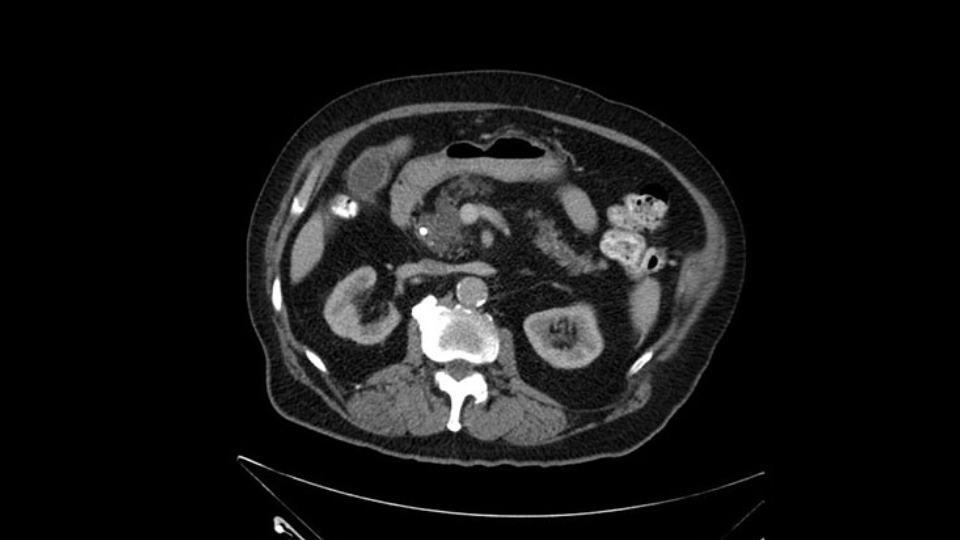

Anyhow. What the surgeon does need to do though, is focus on the resection. What I generally do is look at the tumor, which is here, and then I look at the nature of the pancreas. That’s really just to get an idea on what it would be like to do the pancreatic anastomosis, which isn’t technically the biggest deal, but it’s the biggest deal for the patient afterwards; and the larger the duct and the harder the pancreas, the less likely it’s going to leak. Leaks are what cause almost all the morbidity so I do think of it mentally. I wouldn’t do anything differently, the night before or the morning or the surgery or during the surgery, but certainly mentally it’s useful to know that you may have a challenge in terms of doing the best pancreatic anastomosis you can. I think the duct is quite large. The interesting thing about the duct: it does peter out into fairly normal looking pancreas; that’s a bit strange. But I’ll assume the duct is large.

Then look at the first jejunal branch - which is this thing here - this little branch which goes under the SMA. It’s something that we’ve just started appreciating over the past few years and the reason for that is: there’s two or three small branches that come out of the uncinate into the the first jejunal and it’s a fairly inevitable part of the operation where there’s some bleeding. As long as you’re cognizant of what’s happening, it’s no reason to panic and that kind of bleeding will eventually stop or can be stopped but it’s not easy because these little vessels are fragile from the uncinate to the first jejunal. So I do focus on that and it’s pretty consistent I’d say 9 times out of 10, people have that first jejunal.

I see a dilated biliary system but I also see a dilated pancreatic ductal system which is almost looking cystic in the head and neck region of the body. When I tackle the neck of the pancreas during the course of the surgery, I would have to pay particular attention to the neck of the pancreas when I transect it, to see for any changes of associated IPMN. They may not be IPMN but the thing is there is dilatation and that’s why I need to be careful, with the consideration for intraoperative frozen section for the pancreatic neck margin.

When reviewing the images of this patient, it is striking that there is a large dilation of the Wirsung duct, which is unusual in patients with carcinoma of the ampulla of Vater, and the dilatation in the head of the pancreas has almost replaced all the parenchyma, therefore there is a significant suspicion that the patient has an intraductal papillary mucinous tumor of the pancreas. It’s possible that it's a result of the same pathology and what we are seeing at the ampulla of Vater is the protrusion - because the pancreatic ducts are full of mucus; but we have a biopsy of adenocarcinoma, which could be a malignant degeneration, of an intraductal papillary mucinous tumor or a coincidence pathology, in addition to adenocarcinoma of the ampulla of Vater. Either way, if this patient is having surgery, the decision would be a pancreatoduodenectomy, But we should consider the possibility that the patient might have a intraductal papillary mucinous tumor of the pancreas.

There is a bit of a challenge in my mind that will have to be determined intraoperatively and that's the extent of the pancreatic duct dilatation as you move from the head of the gland more distally into the body and tail. We certainly can see dilatation of the pancreatic duct in patients with ampullary carcinoma. But this seems a little bit unusual in terms of the extended dilatation. It also stops pretty dramatically at the body of the gland with the dilatation not extending to the tail. So again, raises the suspicion that this could be a main duct IPMN. The patient would not require any further preoperative imaging. I don't believe an endoscopic ultrasound is going to add anything to this patient's management. So I would take the patient to the operating room at this time. I would not perform a diagnostic laparoscopy, that's not my practice even for pancreatic cancers at least involving the head of the gland.

After dividing the GDA you're really at the neck of the pancreas and in this case this is where the intraoperative decision making may be a little bit more challenging because as I mentioned, there's dilatation of the pancreatic duct well beyond the normal place where you would divide the pancreatic neck in a standard Whipple. So we would have to mobilize the patient further to the left, probably up to almost to the celiac axis or maybe even beyond as I look at this, it extends almost a centimeter or so into the splenic artery. You could take your chances on this, you could divide it and then do an intraoperative frozen section and at the time of intraoperative frozen section. If the pathologist says yes they see a main duct IPMN in the in the frozen section then I certainly would extend this further to the left until I was able to get far enough and back to normal pancreas. If this is normal ductal epithelium and the patient has a dilatation the pancreatic duct secondary to the ampullary obstruction, you could certainly make the operation technically easier by not extending that far to the left and be left with a generous pancreatic duct for your reconstruction. But I do think in this case, frozen section confirmation that you do not have a main duct IPMN will be essential to determine the extent of resection. I see no reason why this patient would be advised that they're going to need a total pancreatectomy. He does have a generous amount of gland in the body and tail but it will increase the technical difficulty of both resection and reconstruction to get to the left of where that dilatation ends.